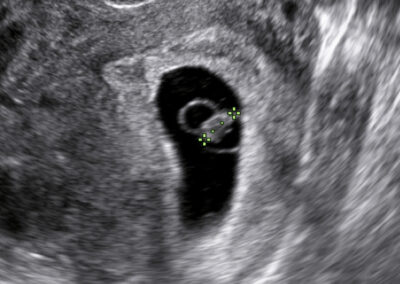

Dear future mother, we provide both basic and specialized ultrasound scans in pregnancy. We use Samsung’s state-of-the-art ultrasound systems and all our doctors are holders of Fetal Medicine Foundation certificates for all types of ultrasound examinations in pregnancy. We follow FMF protocols for fetal examinations and combine 2D with 3D ultrasound scan and assess even subtle anatomical details in order to obtain as precise a result as possible. Throughout the scan, we will keep you informed about the parts of fetal anatomy displayed on the screen. After the scan we will explain to you the results, prognosis and possible further management.

Early pregnancy scan Nuchal translucency scan in 1st trimester Anomaly scan in the 2nd trimester Fetal wellbeing scan in the 3rd trimester